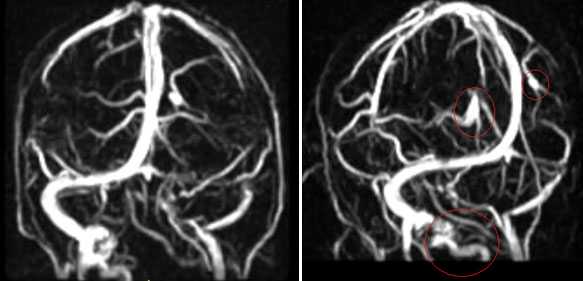

СТЕНОЗЫ, УЧАСТКИ ПАТОЛОГИЧЕСКОГО РАСШИРЕНИЯ И ГИПОПЛАЗИЯ ВЕНОЗНЫХ СТРУКТУР ГОЛОВНОГО МОЗГА

МРА-картина выраженной асимметрии венозной сети с преобладанием и нерезкой дилатацией вен правой гемисферы (поперечного, сигмовидного синусов и яремной вены справа); гипоплазии левого поперечного и сигмовидного синуса. Единичные участки (2) локального расширения вен в парасагиттальных отделах левой гемисферы, большой вены мозга. Асимметричная, расширенная и выражено извитая венозная структура экстракраниальных отделов справа.

МРА признаки незначительной дилатации верхнего сагиттального синуса, локального снижения кровотока и сужения просвета дистальных отделов прямого синуса; асимметрии просвета поперечных, сигмовидных синусов и внутренних яремных вен.